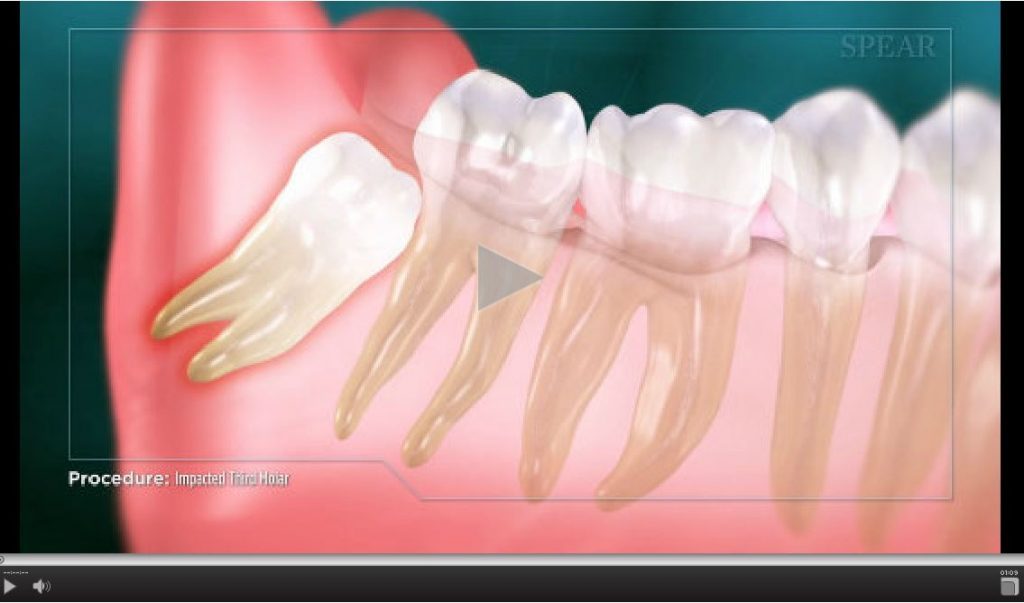

From www.renderhub.com

Impacted Molar 3D Model by esfey What Is Impacted Molar Impacted wisdom teeth that cause pain or other dental problems usually are taken out with surgery, also known as extraction. These teeth typically come in during the late teen years or early adulthood. If you have an impacted tooth and it's causing you discomfort, or your doctor suspects it may lead to dental complications, surgery may be required. Wisdom teeth. What Is Impacted Molar.